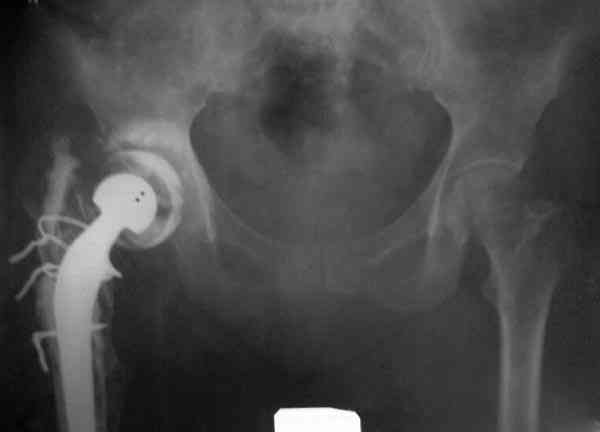

Приглашенный хирург установил ревизионный вариант бедренного компонента без замены ацетабулярного компонента, что осложнилось нагноением и свищами на уровне сустава и средней трети бедра. После двухгодичного безуспешного лечения перевязками и антибиотиками больная обратилась к нам на консультацию.

Для спейсера в бедро использовал старый длинный бедренний компонент меньшего диаметра, облепленный со всех сторон цементом с антибиотиком.

№3-6 снимки с осложнением